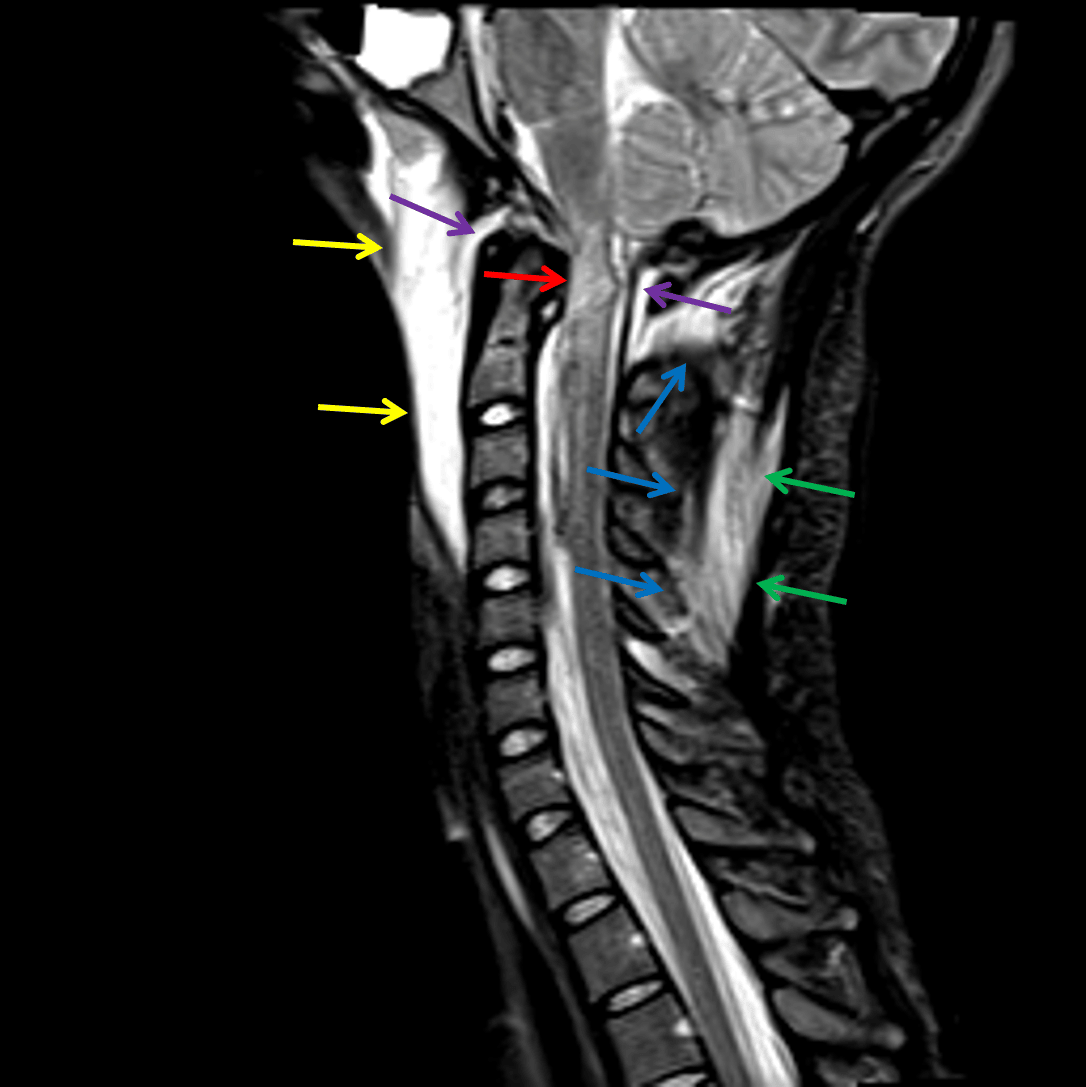

- Many of the stabilizing ligaments can be identified and assessed on MRI, which are shown in the annotated images below

- The two most important ligaments for stabilizing the craniocervical junction are the alar ligaments (which extend obliquely from the dens to the occipital condyles) and the tectorial membrane (the superior continuation of the posterior longitudinal ligament)

Sagittal Cervical Spine Ligaments